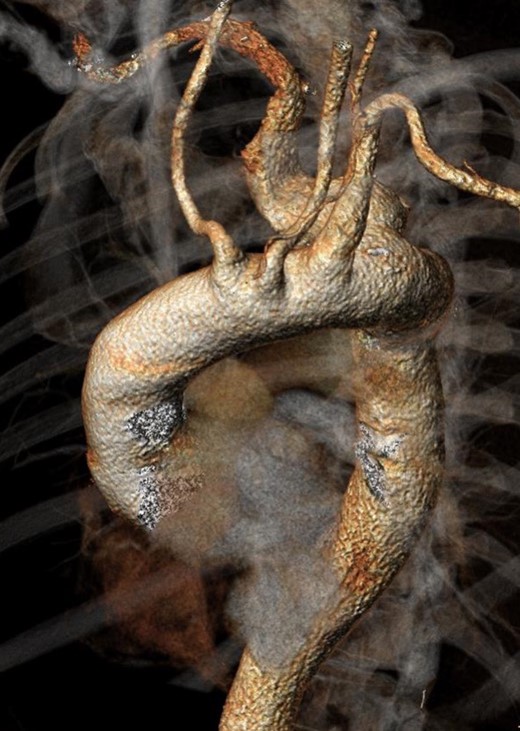

A male patient, aged 73, with a history of hypertension and Pott Disease, was referred to our Unit for dysphagia and incoercible cough. The diagnostic angio-computed tomography (CT) scan showed a retroesophagel AARSA with a maximum diameter of 70 mm, determining the compression of both esophagus and trachea, with a dominant left vertebral artery (Fig. 1). Both aortic arch and thoracic aorta were not involved in the aneurysmal degeneration and no significant intra- and extracranic carotid stenoses were described. A hybrid surgical approach with was planned to exclude the AARSA and to preserve the inflow of both subclavian arteries. It consisted of a bilateral common carotid-to-subclavian artery bypass with a 7 mm expanded polytetrafluorethilene (ePTFE) prosthetic graft and the deployment of thoracic endoprosthesis (Cook Medical Inc, Bloomington, IL ZTA-P-40-117) distally to the left carotid ostium to exclude the aneurysm. The distal neck of AARSA was embolized with a 16 mm Amplatzer vascular plug. Complete technical success without evidence of endoleak was detected at the end of procedure. The embolization of the left subclavian artery at its origin was not performed because the stent-graft completely covered its ostium and it was well adherent to it. The postoperative medical therapy consisted of subcutaneous sodium enoxaparin for the first postoperative month and single antiplatelet treatment indefinitely. The patient was discharged on the ninth postoperative day and underwent angio-CT scan at 1 month (Fig. 2) and yearly thereafter. The 1-year angio-CT scan showed the development of a Type II endoleak from bronchial arteries without significant sac enlargement.